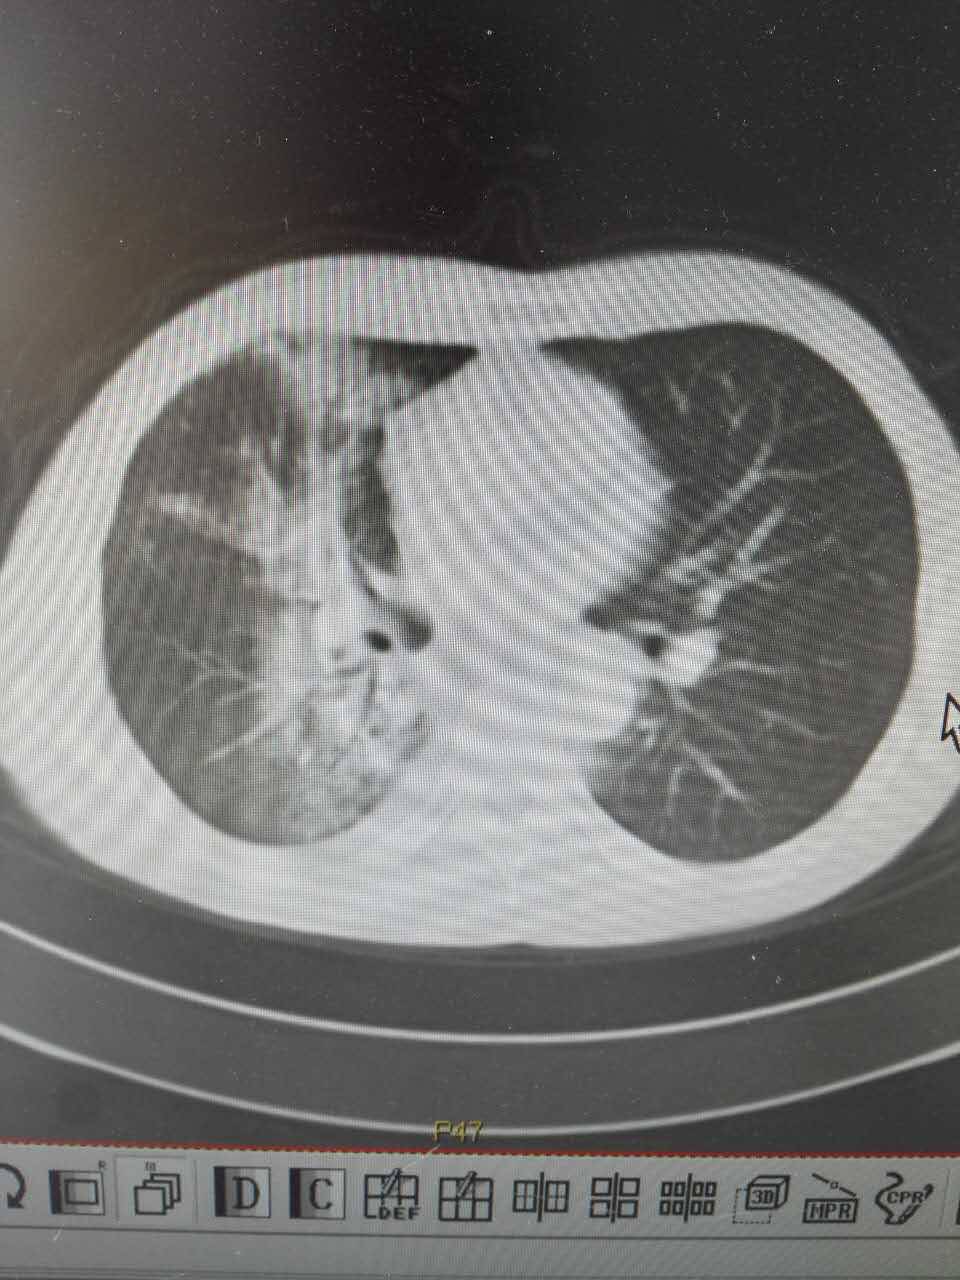

父亲增强CT报告出来了,医生说不是很好(吃克唑替尼才两个多月)

肺部一片一片白色信号,医生说已经看不出来原病灶大小了,说是阻塞性肺炎,该怎么治疗?

颈部淋巴结和肝转症状消失了